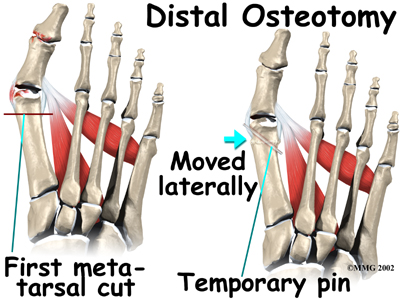

When a surgeon cuts and repositions a bone, it is referred to as an osteotomy. There are two basic techniques used to perform an osteotomy to realign the first metatarsal.

Distal Osteotomy

In some cases, the far end of the bone is cut and moved laterally (called a distal osteotomy). This effectively reduces the angle between the first and second metatarsal bones. This type of procedure usually requires one or two small incisions in the foot. Once the surgeon is satisfied with the position of the bones, the osteotomy is held in the desired position with one, or several, metal pins. Once the bone heals, the pins are removed. Removing of the pins usually occurs between three and six weeks following surgery.